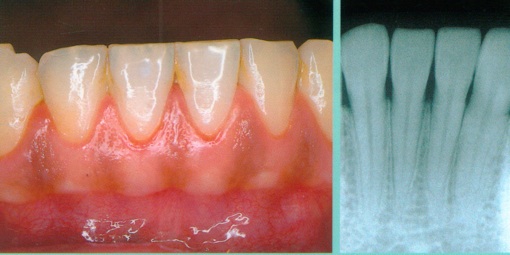

1.検査

歯周ポケットの測定

レントゲン

口腔内写真